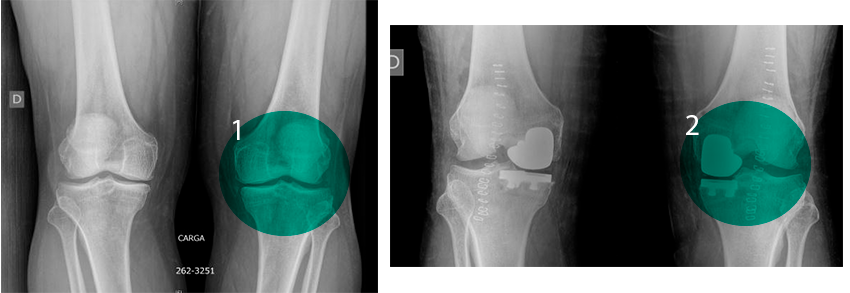

Ergebnis einer partiellen Kniegelenkersatzoperation:

Vorher und Nachher